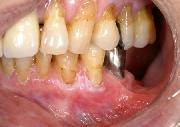

下顎歯肉がん(下あごの歯ぐきのがん)